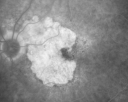

FLUORESCEIN ANGIOGRAPHY: Fluorescein angiography shows concentric geographic atrophy, predominately nasal to the fovea in each eye. The geographic atrophy is unfortunately now closer to the foveal center.